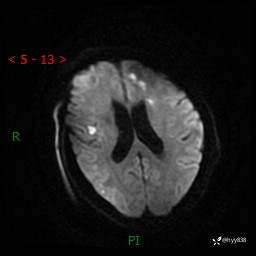

患者性别:女

患者年龄:57岁

简要病史:昏迷入院

临床诊断:昏迷

颅脑MRI(T2WI+DWI)